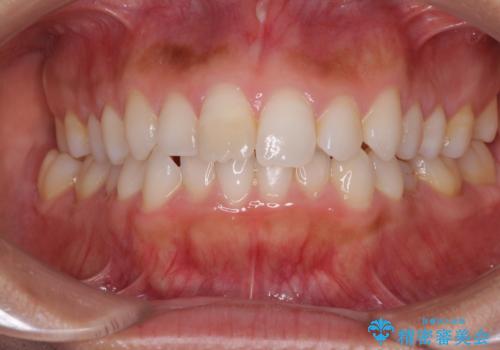

- 上下の前歯のデコボコと奥歯の反対咬合を気にして来院された患者様です。

インビザラインを用い、上下顎ともにIPR(歯と歯の間を削る)により叢生を改善することとしました。

奥歯の反対咬合は、骨格に由来するものであるため、改善できるところまで改善していくこととしました。